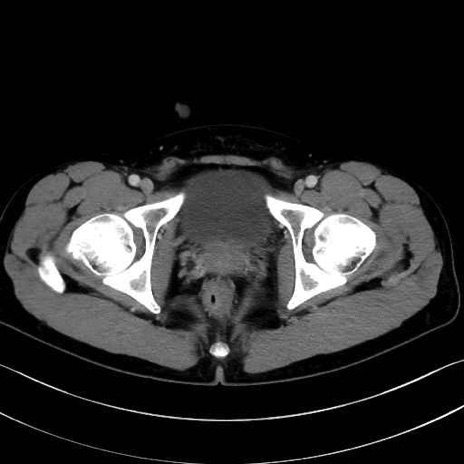

大腿方形筋 (Quadratus femoris)

5. 大腿前面(大腿四頭筋群・伸筋群)

縫工筋 (Sartorius)